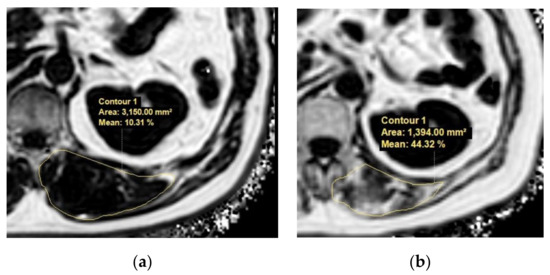

Generally, the cross-sectional areas of the psoas or abdominal muscle mass of the third (L3) or fourth (L4) lumbar vertebra levels that are not affected by activity are used. Although the cross-sectional area of the level of the umbilicus has previously been used [26], this area may be measured at different levels of the vertebra. Moreover, the umbilicus may become flat and unable to be found on axial CTs in patients with ascites or obesity [43]. Measuring should be conducted at the cross-sectional area of the skeletal muscles at the level of L3, which accurately represents the whole-body skeletal muscle mass [44]. At the L3 transverse section, muscle groups include the rectus abdominis, transverse abdominis, internal and external obliques, quadratus lumborum, psoas major and minor, and erector spinae. These measurements were computed by summing the tissue pixels and multiplying them by the pixel surface area. A threshold range of 29 to 150 HU is commonly used to define the muscle (Figure 3).

Figure 3.

Abdominal CT images taken at the third lumbar vertebra with cirrhosis applied to quantify transverse psoas muscle thickness (TPMT), psoas muscle, and total muscle areas. The psoas muscle in panels (c,d) and total muscle area in panels (e,f) are colored in red. Panels (a,c,e) present a female patient with low TPMT (5.9 mm/m), psoas muscle index (PMI) (2.3 cm2/m2), and skeletal muscle index (SMI) (35.7 cm2/m2). Panels (b,d,f) present a male patient with high TPMT (23.3 mm/m), PMI (6.8 cm2/m2), and SMI (51.6 cm2/m2). The mean density of muscle in (c–f) is 34.7, 38.2, 26.2, and 36.6 HU, respectively.